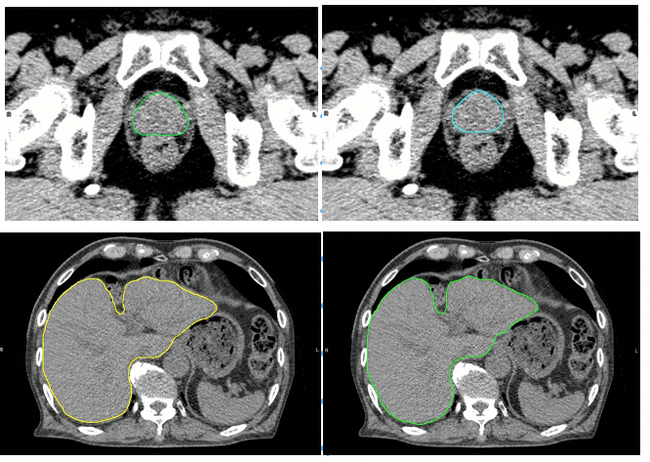

肝臓モデルを使用した例では,輪郭作成に要する時間は,従来の手作業のみでは30分以上要したものが,臨床利用ための人による修正時間も含め,Ai-Segによる自動輪郭作成及び必要に応じての軽微な修正作業を合わせて5分程度までに短縮することができた。図1に示すように医師とAi-Segが作成した輪郭を比較しても違いがわからないほどの水準にまで達している。

図の上は前立腺,下は肝臓のCT画像。左はAi-Segによる自動抽出,右は医療従事者の手入力による抽出。Ai-Segによる描画は医療従事者による描画と遜色ない精度で輪郭を自動作成が可能(図の提供:大阪大学プレスリリースより※)